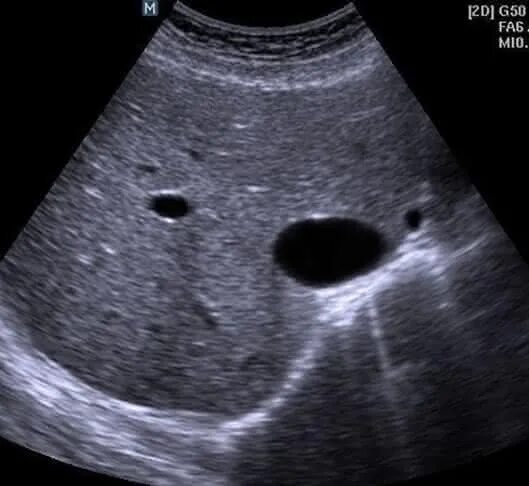

Белое пятно на узи